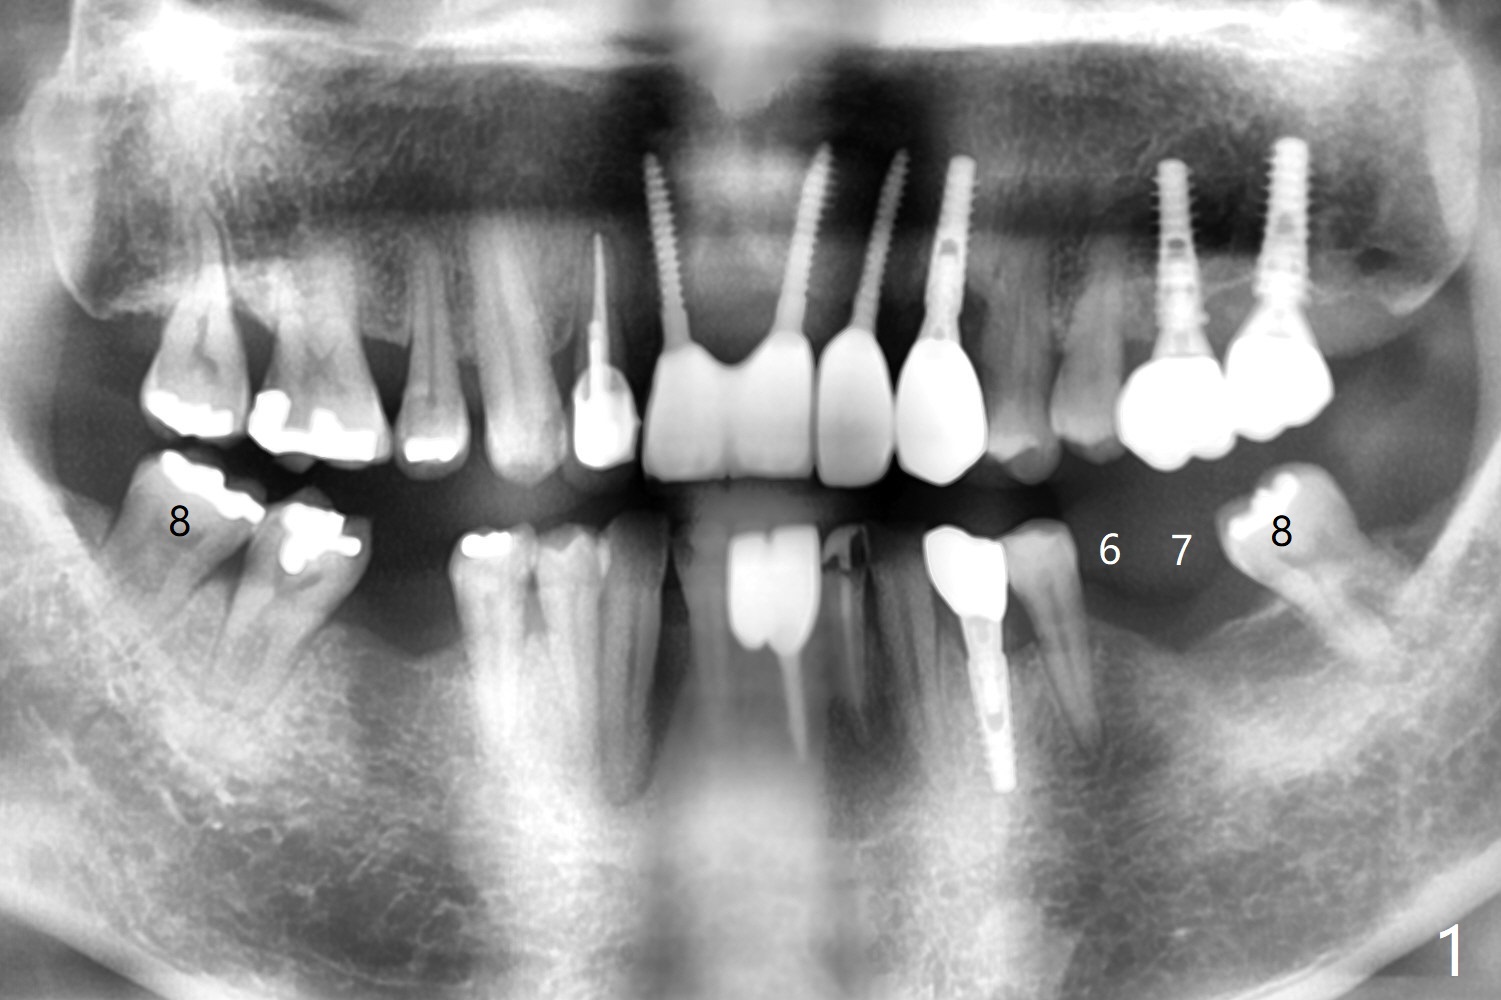

56岁男,高血压,紧张怕痛,要求迅速手术,所以我们初步选择导航。由于他还能在右边咀嚼,先做左侧植牙。左侧好像缺失两个牙齿(图一),不过近远中间隙更象缺失一个牙齿(图二)。牙槽嵴狭窄,骨皮质厚,容易植骨吗?还是容易劈开?牙槽嵴狭窄(图三,四,六)似乎适合种植两个小植体(两个双尖牙)。如果只植入一个,牙槽骨高度差些,植体短(图五),仿佛做牙槽嵴劈开术比较好。